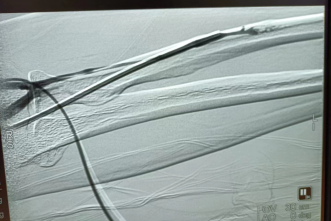

3月30日,肾病内科副主任、副主任医师杨帆带领团队在超声诊断科的配合下,行左上肢血管造影,找到了“罪魁祸首”。超声显示:内瘘静脉中段管腔局部增厚,最厚处约2.8mm,累及长度约17.2mm,局部管腔变窄,最窄处约1.4mm。术中造影也提示内瘘静脉局部重度狭窄,若不及时治疗,可能很快会出现内瘘闭塞。随后,在DSA引导下,杨帆副主任团队顺利完成患者狭窄血管的扩张。

扩张前造影

术中扩张局部狭窄 狭窄扩开后